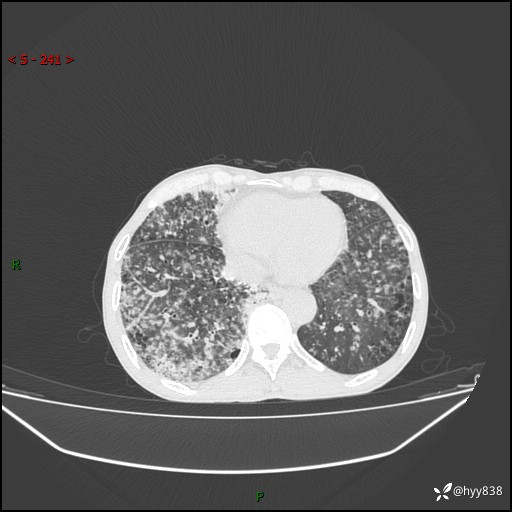

胸部CT平扫